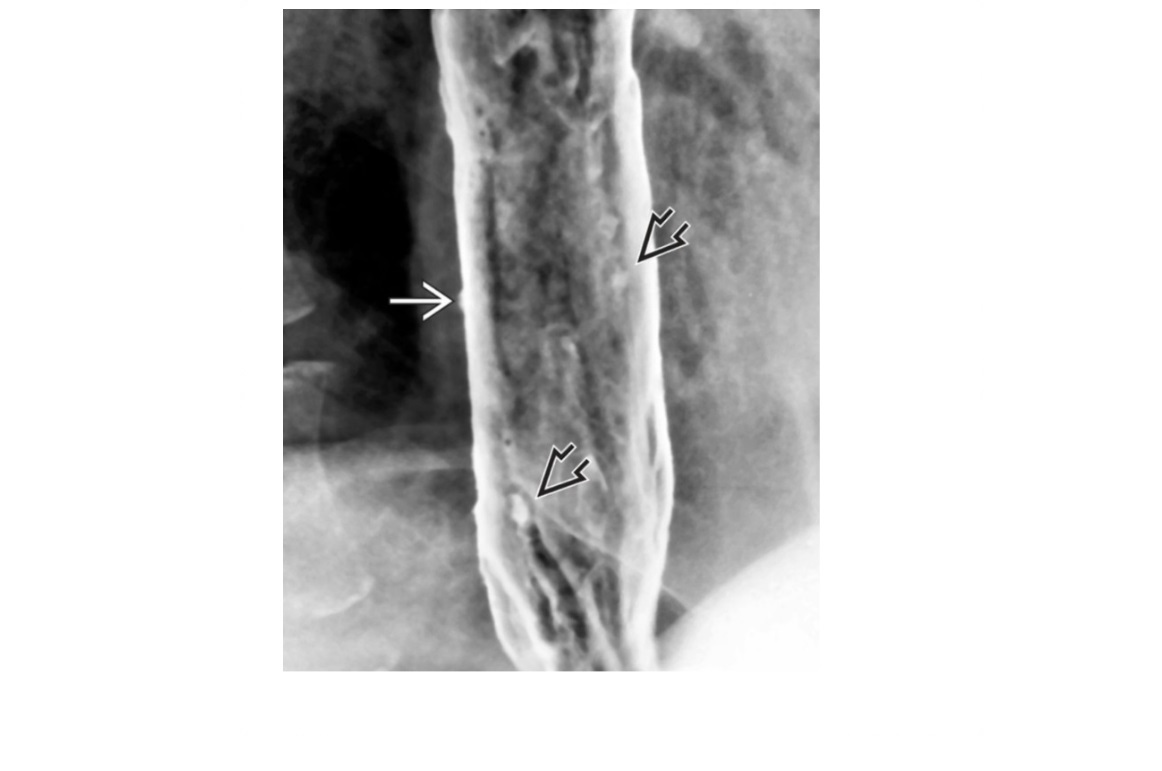

Oesophageal pseudodiverticulosis

Barium - multiple, tiny (1- to 4-mm depth), flask-like outpouchings in the oesophagus

Barium trapped in dilated excretory ducts of submucosal glands

CHRONIC REFLUX* and Candida